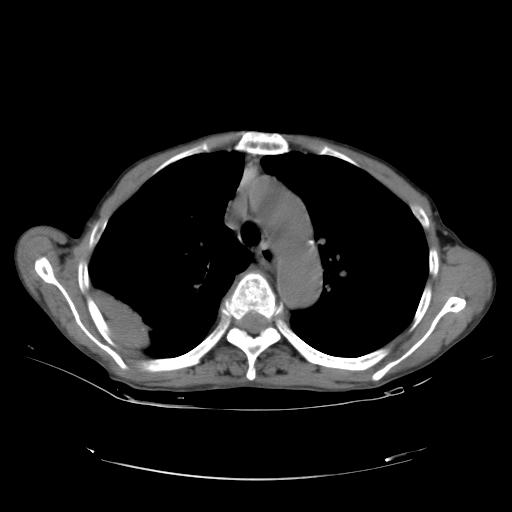

女,72岁,咳嗽一周余,突发右下肢无力二天。

pe:bp-140、80mmhg,精神可,伸舌居中,右上肢肌力正常,右下肢肌力0级,巴氏征+

来院做头颅+胸部ct平扫

遂加作增强:

胸部病变平扫35hu,增强强化至70hu

这个病人首先是胸部病变的定位到底是肺内还是肺外。仔细观察块影位于胸膜下,与胸膜间有透亮带,且近端血管未见明显推移而是引流样改变,形态分叶,说明这个病灶位于肺内胸膜下。很可能是腺癌,腺癌最易致颅内高密度转移灶。局部胸膜有侵犯。

本例颅内见多发大小不等高密度灶,有强化及水肿;另外,胸锁关节层面可能是第四胸椎及右侧肋骨起始部骨质欠连续,椎旁软组织肿胀,建议调骨窗观察。

基于以上原因,所以炎性肿块或胸膜间皮瘤不考虑。

诊断:右下肺癌伴颅内、胸椎、肋骨转移可能性最大。